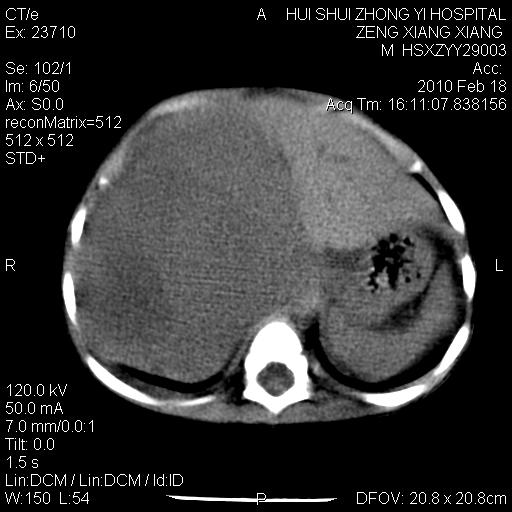

标题: PED3106:男,2岁,腹胀1月。 [打印本页]

标题: PED3106:男,2岁,腹胀1月。

定位腹膜后,肾上腺来源;

定性:恶性神经源性,肾上腺神经节母细胞瘤可能性大。

鉴别:肝母、肾母、肝脏中胚层错构瘤。

依据:年龄、有钙化,肾脏及肝脏受压移位。